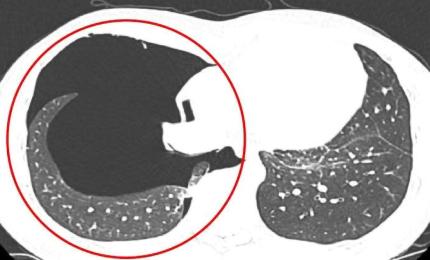

Sáng 9/11, nam công nhân có biểu hiện đau ngực trái, khó thở dữ dội sau khi lặn sâu khoảng 11 mét.